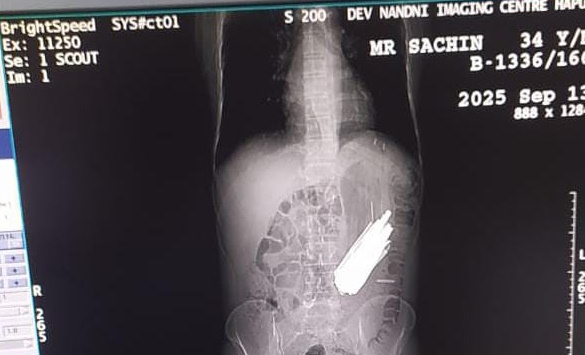

हापुड़ जिले में एक चौंकाने वाली घटना में एक 40 वर्षीय नशे के आदी व्यक्ति सचिन के पेट से ऑपरेशन के दौरान 29 चम्मच 19 टूथब्रश और दो पेन निकाले गए। बुलंदशहर के रहने वाले सचिन को नशा मुक्ति केंद्र में भर्ती कराया गया था जहां नशा न मिलने पर उसने ये चीजें निगल लीं। पेट में दर्द होने पर अल्ट्रासाउंड और एक्सरे से मामले का खुलासा हुआ।

जागरण संवाददाता, हापुड़। उत्तर प्रदेश के हापुड़ जिले से एक हैरान करने वाली खबर सामने आई है। यहां एक मरीज के पेट से ऑपरेशन के दौरान 29 चम्मच निकली हैं। इतना ही नहीं 19 टूथब्रश व दो पेन भी निकले हैं।

बताया गया कि 40 वर्षीय सचिन बुलंदशहर का रहने वाला है और नशे का आदी है। वहीं, ऑपरेशन करने वाले चिकित्सक भी पेट में चम्मच और टूथब्रश देखकर हैरान रह गए। उसे नशा मुक्ति केंद्र में भर्ती था। वहां नशा न मिलने पर उसने यह सभी चीजें निगल लीं।

इसके कुछ समय बाद पेट में दर्द होने और तबीयत खराब होने पर उपचार कराया गया। पेट के अल्ट्रासाउंड व एक्सरे जांच कराने पर चिकित्सकों को जानकारी मिली थी। शहर के एक निजी अस्पताल में चार घंटे चले ऑपरेशन के बाद यह सब सामान निकाला गया।